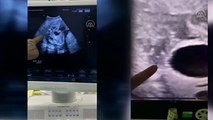

Konya'da 30 haftalık kız bebeğin anne karnındayken gerçekleştirilen cerrahi operasyonla yumurtalık kisti alındı http://www.cumhuriyet.com.tr/video/video/142331/Anne_karnindaki_bebege_ameliyat.html